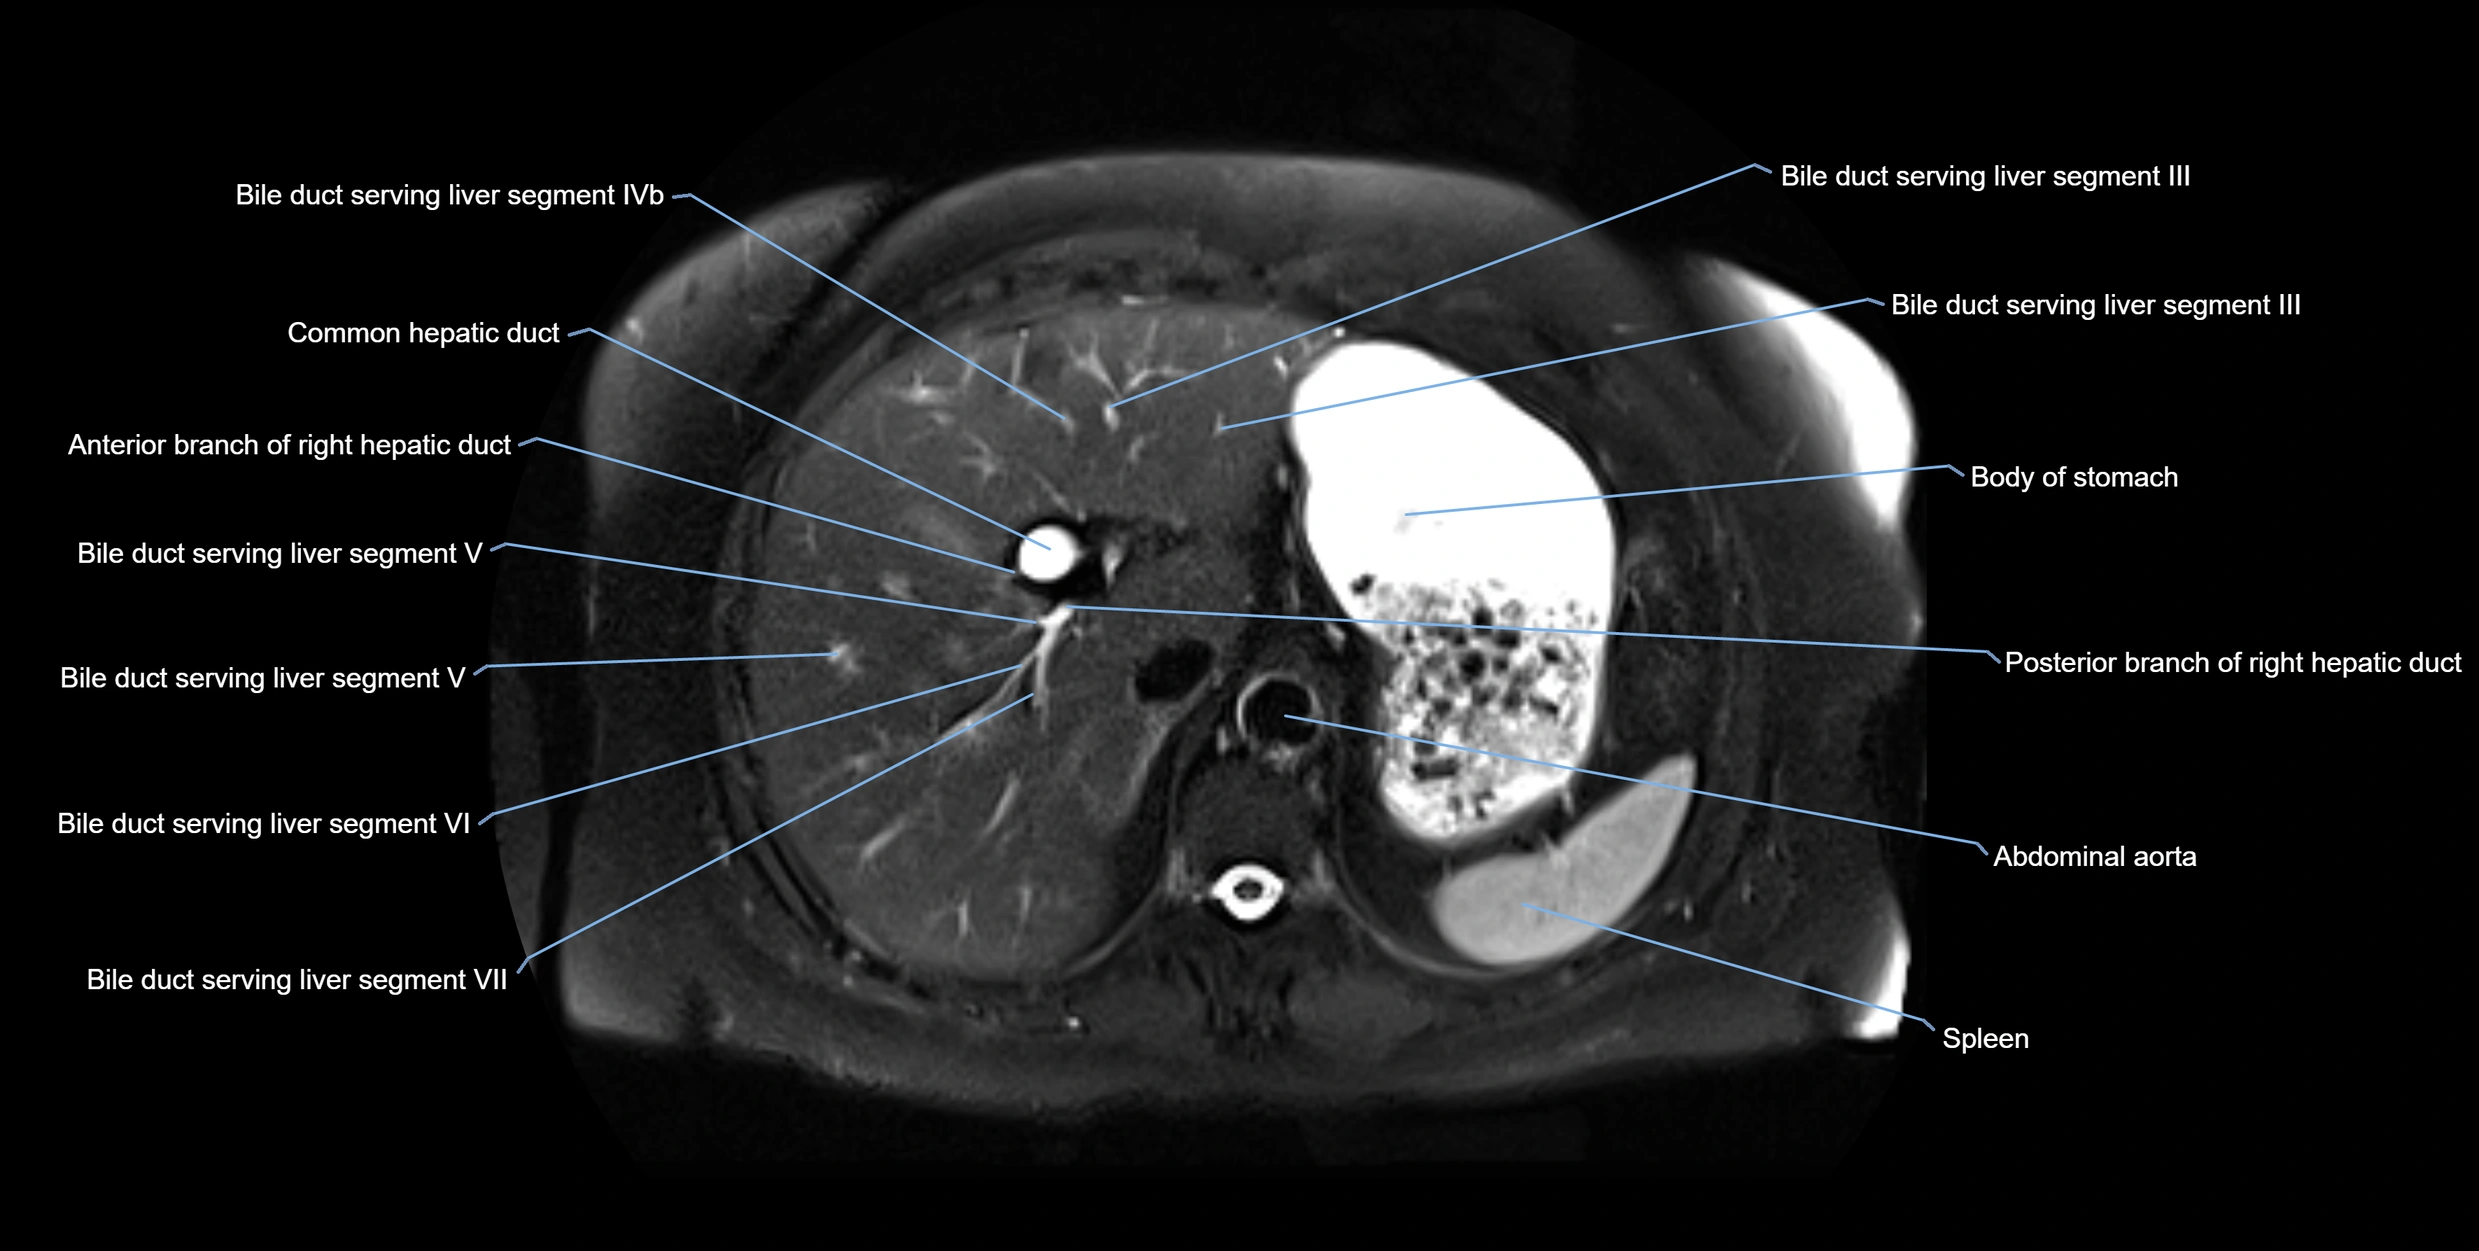

MRI image

image